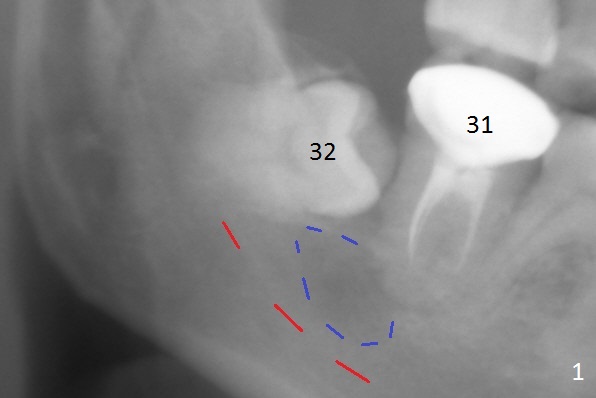

A 45-year-old woman presents to clinic with swelling and pain from the lower right posterior region. The tooth #32 is fully bony impacted. The distolingual gingiva of #31 is erythematous with deep pocket. The tooth is sensitive to percussion. Preop panoramic X-ray shows a radiolucent lesion between #31 and #32 (Fig.1 blue dashed line). Initial impression is infection from #32. Extraction of the latter turns out to be difficult. Purulent discharge is coming from underneath the coronal portion of the tooth. Curettage of the radiolucent lesion leads to hemorrhage. The curettage is not aggressive because of the underlying Inferior Alveolar Canal (red dashed line). Following copious irrigation, a 10x20 mm Osteogen plug is inserted into the socket with incision closure. Postop PA reveals that the roots the teeth #31 and 30 approximate to each other (Fig.2 R). In case the tooth #31 needs to be removed (Fig.3 black area), osteotomy for immediate implant will be established in the middle of the septal stump (Fig.5 red arrow) after removal of the coronal septum (Fig.4). CBCT may be necessary for determination of the osteotomy depth.